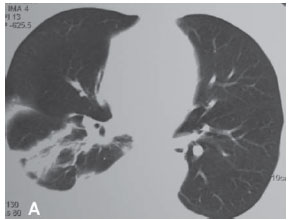

Uma mulher de 63 anos, do lar, não tabagista, previamente hígida, apresentou-se com queixa de aumento de volume em pescoço, face anterior do tórax, abdome e membros inferiores. Havia associação com dispnéia discreta aos esforços. O quadro teve início após atividade física leve em academia de ginástica, havia cinco dias. Negava doença pulmonar prévia e referia uso de fluoxetina a 20 mg/dia, bromazepam a 3 mg/dia e reposição hormonal feminina regular. Ao exame clínico observou-se um discreto aumento de volume em fossa supraclavicular esquerda e face lateral direita do pescoço. Observou-se ainda diminuição do murmúrio vesicular de forma difusa e de frêmito toracovocal em bases (direito maior que esquerdo), além de edema de parede abdominal anterior e de membros inferiores (grau I/IV). Foram solicitados hemograma, coagulograma, glicemia, creatinina, uréia, velocidade de hemossedimentação, colesterol total, HDL, triglicerídeos, T3, T4, TSH e parcial de urina, os quais se apresentaram todos normais, descartando a presença de dislipidemia, coagulopatia, infecção, nefropatia e hipotireoidismo. A avaliação radiológica do tórax revelou um pequeno derrame pleural bilateral (Figura 1), confirmado pela tomografia axial computadorizada de tórax (Figura 2A). Esta foi complementada com cortes ao nível do pescoço, que evidenciaram edema na região supraclavicular esquerda com imagem hipodensa (20 x 10 mm) adjacente ao feixe vasculonervoso do pescoço (Figura 2B). A ultra-sonografia da região cervical mostrou a formação de uma coleção cística, posteriormente aos vasos cervicais, sugestiva da ruptura do tronco jugular esquerdo. Demonstrou ainda um pequeno aumento da espessura do músculo esternocleidomastóideo esquerdo, sugestivo de processo inflamatório secundário a distensão muscular (Figura 3). A paciente foi submetida a toracocentese diagnóstica à direita com obtenção de líquido leitoso compatível com QT. A análise laboratorial demonstrou tratar-se de um exsudato com predomínio de polimorfonucleares e com dosagem de triglicerídeos de 2.035 mg/dl, colesterol de 131 mg/dl e proteínas de 9,7 g/dl, confirmando o quadro laboratorial de QT. Foram realizadas citologia oncótica, bacterioscopia de Ziehl, micológico direto e culturas, que resultaram negativos, descartando processos malignos e doenças infecciosas.